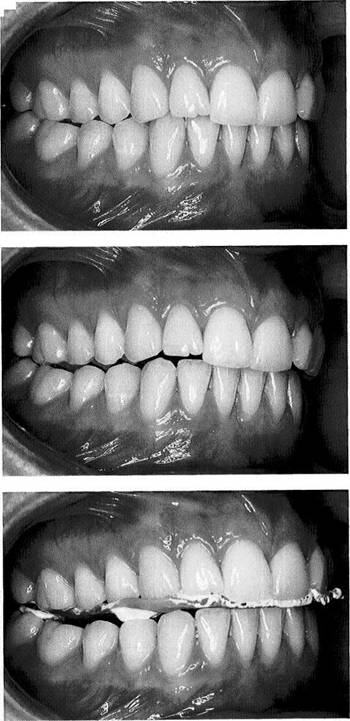

Patients with all their teeth, or at least with upper and lower teeth occluding in all quadrants, offer a stable foundation for the occlusal registration provided there is no abnormal tooth mobility. This is advantageous for precise transference of the intraoral relationships to the casts. Basically, because all antagonistic tooth contacts must be avoided as the occlusal registration is being made, an excessive vertical dimension will result unless all the teeth have been pre­pared for crowns, or the vertical dimension must be increased to restore an abraded dentition. The occlusion should be opened as little as possible consistent with the

properties of the registration material. Prior to making the interocclusal record, the masticatory muscles should be deprogrammed by placing cotton rolls in the premolar regions or by some other method. The actual registration is accomplished in two steps:

Construction of a horizontal bite plane to oppose the

lower incisors.

Occlusal registration in the posterior region.

Multiple interocclusal records used with the split cast method (see p. 230) can provide information on the neuro­muscular stability of the recorded position.

Trimming of the record base

In this example, a prefabricated metal plate (by Panadent) is used in making the registration. After the patient has closed the teeth firmly on the plate, it is trimmed back to the width of the maxillary dental arch. Sharp angles are rounded over with a carborundum stone.

Interocclusal correction of the record base

The metal base is loaded with a reg­istration paste capable of reproduc­ing fine details (here: Super Bite) and placed against the upper teeth. Adhesion of this registration paste to the metal base can be increased by first coating the metal with a sil­icone adhesive.

Next an anterior bite index is formed with green stick compound (by Kerr). Finally the occlusion of the mandibular posterior teeth is registered with more fine-detail bite-registration paste.

Testing the fit of the occlusal record on the casts

To be able to critically examine the occlusal record for exactness of fit while the patient is still present, the casts should already be on hand when the jaw relation record is made. The sides of the tooth im­prints are trimmed back with a scalpel under magnifying loupes. The casts must seat into the record with no gaps.